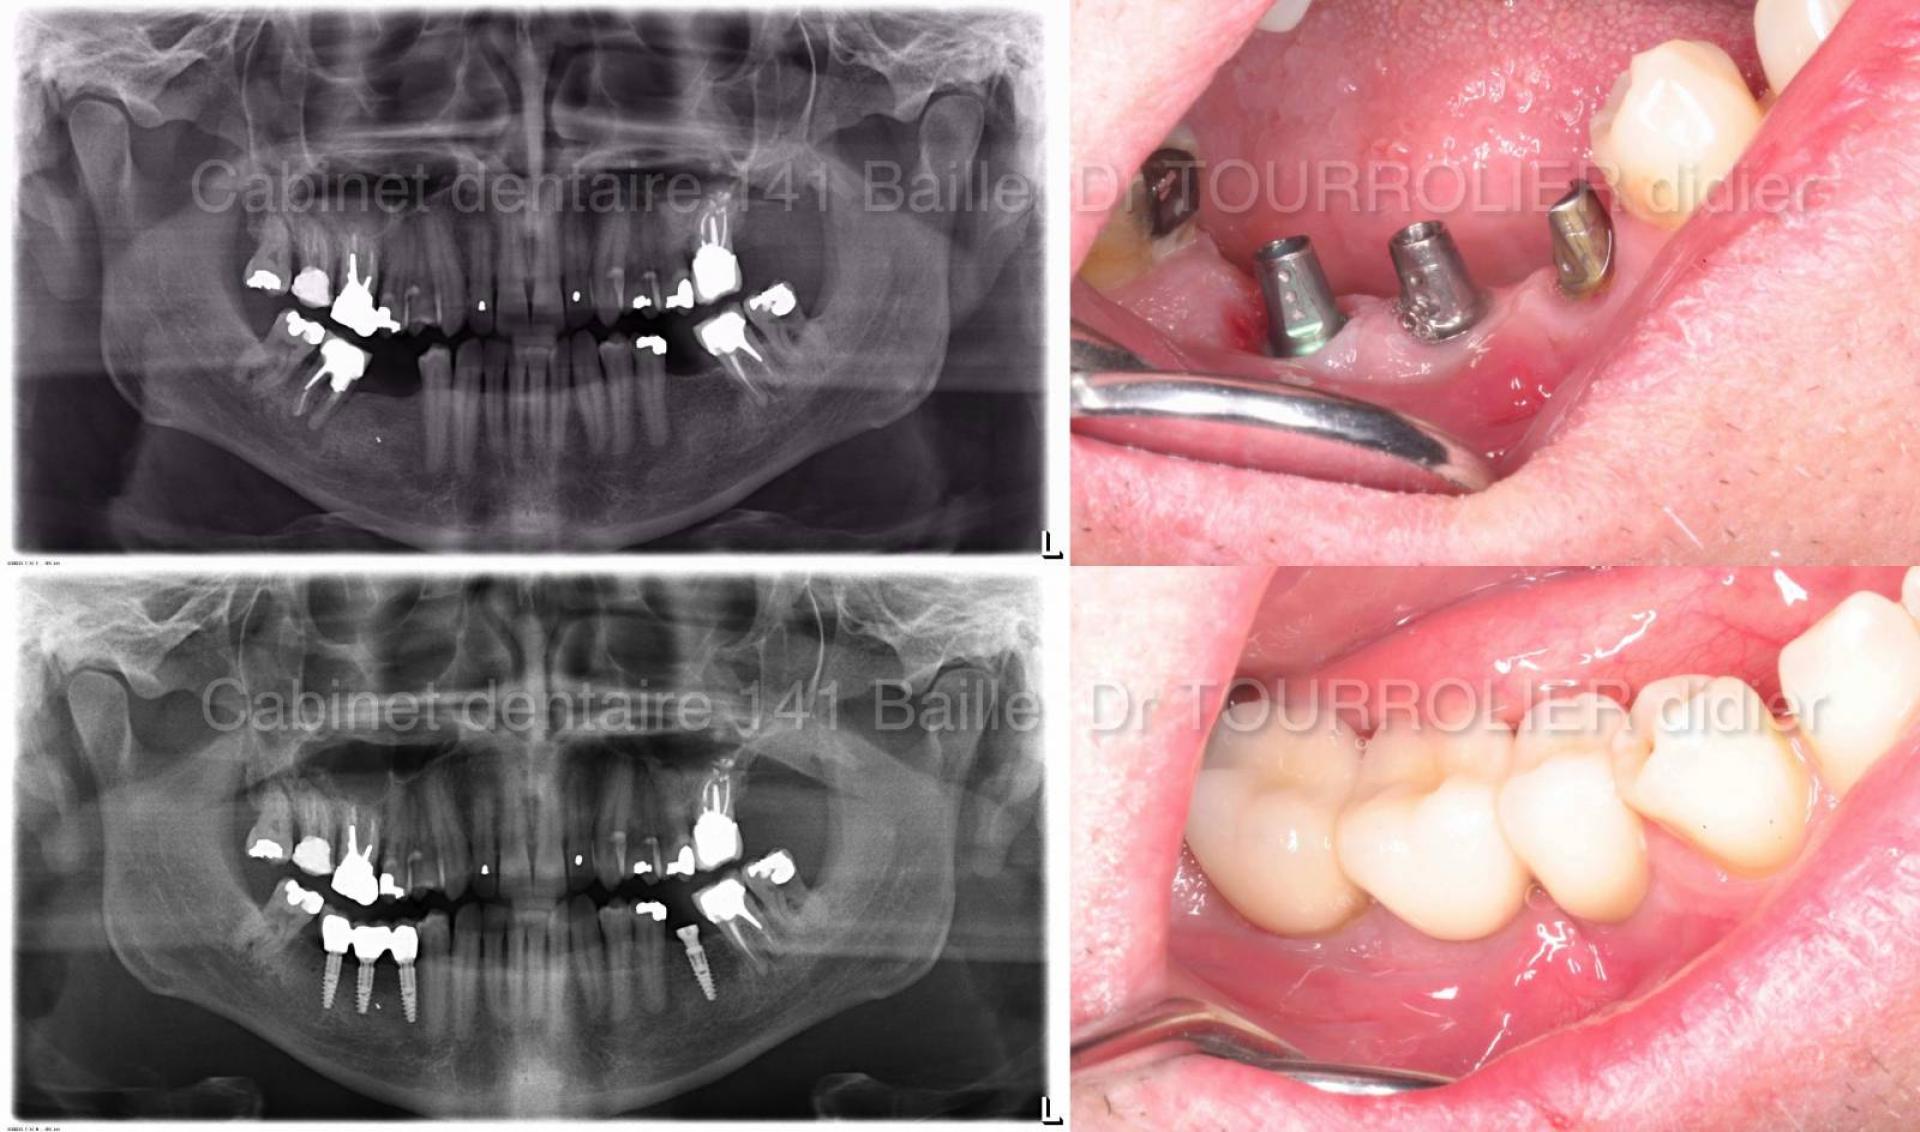

Nous procédons à l'extraction de la dent infectée et au curetage de la zone kystique .

Quand le volume osseux résiduel le permet ,l'implant dentaire sera mis en place le jour de l'extraction.On parle alors d'une chirurgie d'extraction Implantation immédiate.

Nous réalisons systématiquement une greffe osseuse encore appelé comblement osseux .Des granulés d'os (BIO-OSS) sont tassés dans le déficit osseux .

Une membrane résorbable de type PRF ou Biogide sera mise en place et stabilisée avec des pins chirurgicaux qui sont de petits clous de stabilisation.

La mise en charge de l'implant se fera au bout de 3 mois afin que le processus d'ostéointégration puisse s'effectuer.